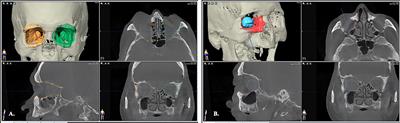

in Veterinary Dentistry and Oromaxillofacial Surgery